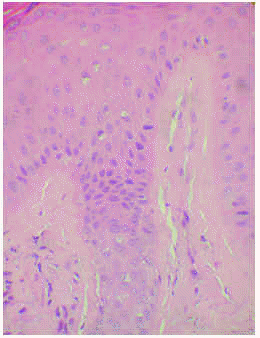

La biopsia cutánea mostró una epidermis con hiperqueratosis homogénea sin paraqueratosis y mínimo infiltrado inflamatorio. Se observaban múltiples amastigotes en el interior de los queratinocitos, con degeneración vacuolar y libres a todos los niveles de la epidermis, incluyendo la capa granulosa y entre la queratina de la capa córnea. También se observaron en menor proporción en el conducto excretor ecrino y en el acrosiringio. En la dermis y la hipodermis se apreciaban múltiples organismos intra y extracelulares, entre los haces de colágena, alrededor de las glándulas ecrinas, entre los adipocitos y alrededor de los vasos sanguíneos (figs. 2 y 3).

Fig. 2.--Numerosas leishmanias a todos los niveles de la epidermis, incluida la granulosa y entre la queratina de la capa cornea. (Hematoxilina-eosina, x400.)